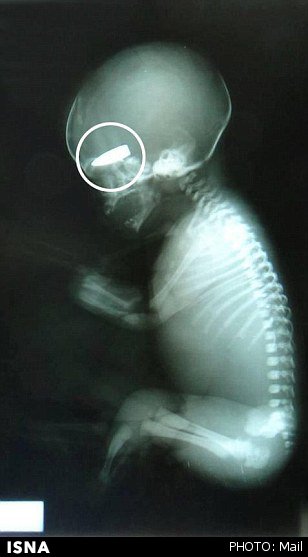

وی گفت: روزی در کلینیک بودم و دو زن باردار را که از ناحیه شکم هدف تک تیرانداز قرار گرفته بودند، به این مکان منتقل کردند. زنان از ناحیه رحم مورد هدف قرار گرفته و جنین آنها کشته شده بود.